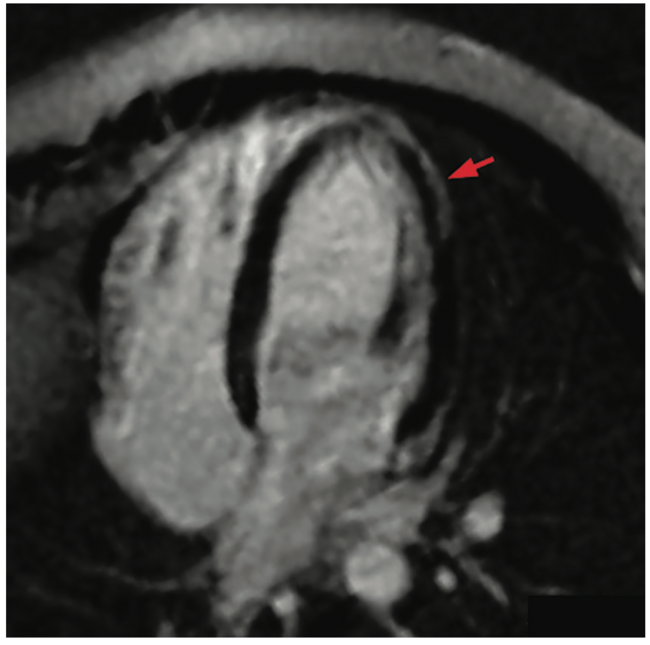

Finally, detection of isolated CMR findings may be encountered, such as late gadolinium enhancement (LGE) without concomitant edema.13,20,21 In those with a suspicion of myocarditis or supportive abnormal findings on triad testing, this may be representative of resolving myocarditis.22-24 Athletes may have mildly reduced left ventricular (LV) systolic function, isolated mild troponin elevation, or an abnormal ECG. This can be the result of an exercise-induced cardiac remodeling or a pathologic expression of myocarditis.25 Involvement of experts in the field of sports cardiology is recommended, when possible, to help determine pathologic vs physiologic change is present. If pathologic change is less likely, consider maximal-effort exercise testing (including stress echocardiography if there is reduced LV systolic function to assess for appropriate exercise augmentation)26 and ambulatory rhythm monitoring.

In those with documented clinical myocarditis, existing guidance regarding sports eligibility recommends 3-6 months of complete exercise abstinence.27 There is no clear recommendation for how to determine the exact RTP strategy, but should be based on resolution of cardiopulmonary symptoms and laboratory evidence of cardiac inflammation, normalization of LV systolic function, and absence of inducible cardiac arrhythmias. Whether this 3-month minimum of exercise abstinence independently reduces the risk of acute cardiac events is uncertain. In the Big Ten COVID-19 Cardiac Registry, 27 athletes (27/37, 73%) with clinical or subclinical myocarditis completed repeat CMR within 4-14 weeks after initially testing positive for COVID-19.13 In 11 of these athletes (41%), LGE and T2 mapping abnormalities had completely resolved after a median of 8 weeks.13 Whether this resolution equates complete inflammation without underlying subclinical findings is unknown. These data suggest that it is reasonable to reassess for resolution of myocardial inflammation in those with clinical myocarditis <3 months since testing positive for COVID-19, especially if they have had rapid resolution of symptoms and prior demonstration of normal LV systolic function, or in those with subclinical myocarditis identified with CMR screening. The best time for this reassessment likely should be individualized, but no sooner than previously recognized. For asymptomatic athletes with complete resolution of myocardial inflammation and no spontaneous arrhythmias, a RTP approach using conservative, graded exercise should be pursued. Further research is required to define the temporal pattern of myocardial inflammation, along with predictors of clinical myocarditis progression among all viral pathogens with affinity for the heart.